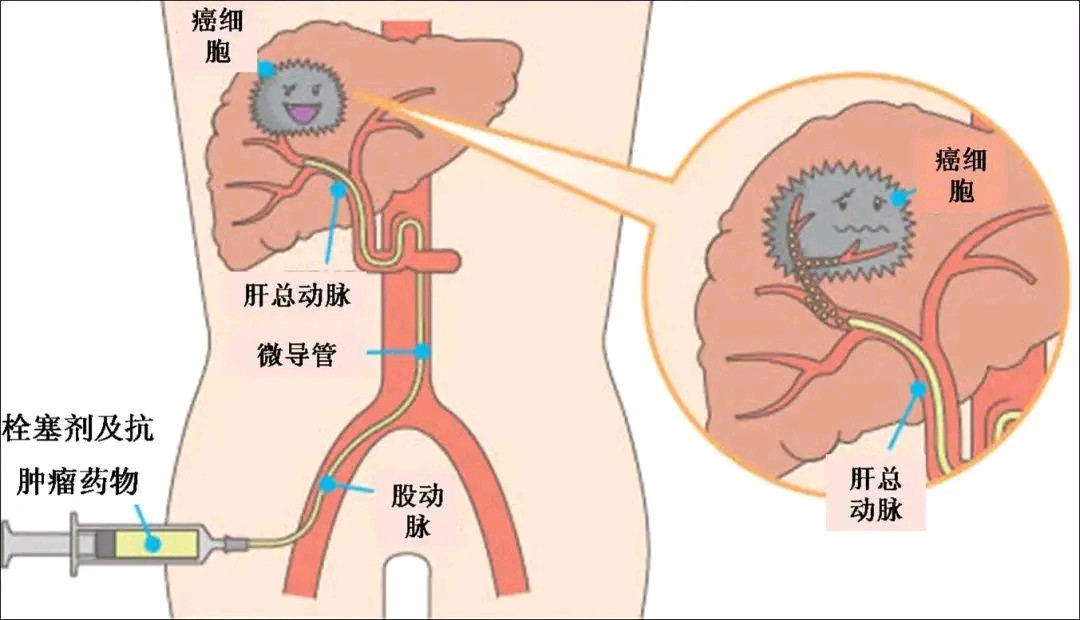

肿瘤化疗栓塞是常见的介入手术,又称为TACE,英文全称为transcatheter arterialchemoembolization,是将特制的导管等介入器材,经血管送至病变相关部位,先注入造影剂行血管造影,了解病变区域的解剖及病理结构变化,以明确诊断;再将导管插至肿瘤供血血管内,经导管向肿瘤内注入能杀死肿瘤细胞的化疗药及可阻断肿瘤血供的栓塞剂,以期“毒死”和“饿死”肿瘤。该技术属于微创治疗的一种,不需要开刀,不用全麻,只需要通过在大腿根部穿刺血管(常规是股动脉),手术创口仅2mm左右,可以对全身大多数脏器的实体肿瘤进行治疗,属于一种微创绿色疗法。